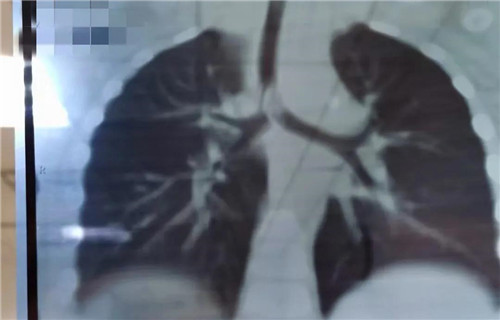

22日晚,19个月女宝诺诺(化名)在家吃花生突然呛咳,爸爸把她倒过来拍几下,诺诺吐出半个花生,但没好转,又出现喘憋,情况非常紧急......夫妻俩立即带孩子来到蜜桃视频 就诊,耳鼻喉科夜班医生接诊。医生初步判断是气管异物,而且很可能在主气道。肺CT三维重建显示,异物正堵在主支气管与分叉气管交接口,基本堵满了,诺诺出现吸气性呼吸困难。情况紧急,考虑急诊手术取出。当晚9点多,诺诺住院。此时,耳鼻喉科主任沙颖、副主任李莉萍、刚加完班回家的李萍大夫,麻醉科主任王丽波也正在从家往医院赶。

当晚12点,诺诺进入手术室。因为异物占据气道,孩子又小,取异物一定要快。支气管镜进入后显示,半个完整花生堵在主支气管分叉位置,堵塞面积达到4/5以上,仅在花生边缘与气管之间留有少许通气的地方。花生已经被浸泡得很软了,异物钳夹过程中,不能完整夹持,抓出来的都是或大或小的碎块。随着一块一块碎花生被取出,诺诺的呼吸渐渐地好了起来。诺诺被推回病房时,已经快凌晨2点了。